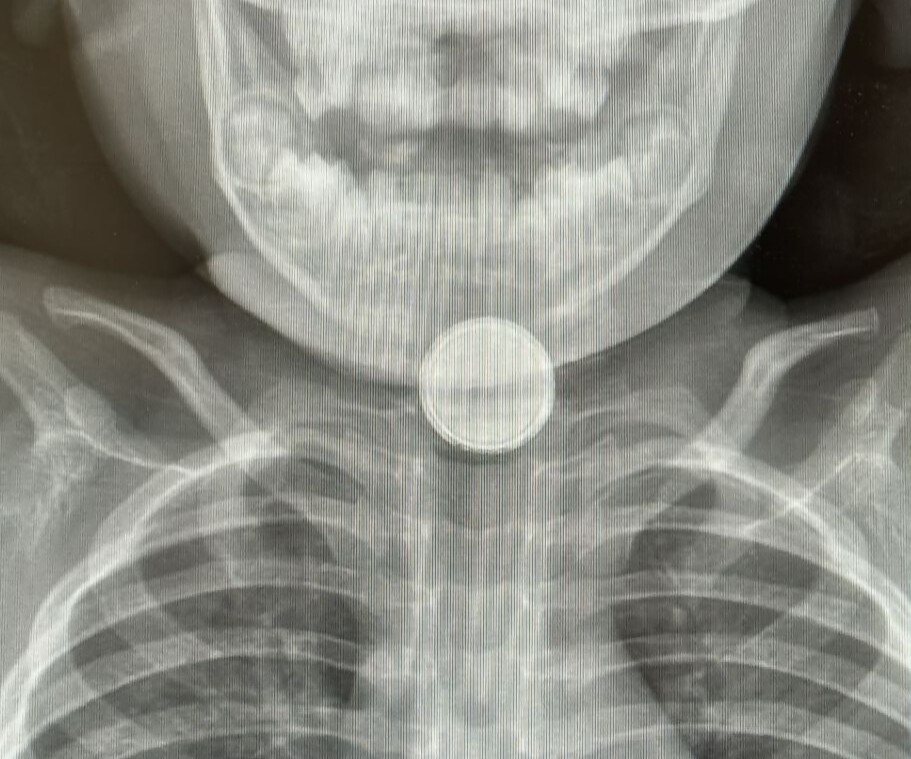

דיווחים מדאיגים מבית חולים סבן לילדים בבאר שבע: מספר ילדים נזקקו לאחרונה לטיפול חירום בעקבות בליעת סוללות כפתור – חלקם במצב קשה

במרכז הרפואי סורוקה בבאר שבע מדווחים על עלייה חדה במספר מקרי בליעת סוללות בקרב ילדים – תופעה מוכרת ומסוכנת במיוחד בגיל הרך. בשבועות האחרונים הגיעו לבית חולים סבן לילדים מספר ילדים כשהם סובלים מפגיעות פנימיות קשות בעקבות בליעת סוללות קטנות, המוכרות מסוללות כפתור המשמשות שלטים, צעצועים, מפתחות רכב ועוד.

המקרה החמור ביותר שנרשם לאחרונה היה של פעוט בן שנתיים שהובהל לחדר ההלם כשלושה ימים לאחר שבלע סוללה – באיחור מסוכן. הוא נזקק להתערבות חירום בחדר ניתוח, ועדיין לא ברורה מידת הנזק שנגרם לוושט ולכלי הדם הסמוכים. במקרה אחר, ילדה בת 7 פונתה תוך זמן קצר אך כבר הספיקה להיפגע – החומר הכימי החל להתפשט באזור כלי הדם, והצוות הרפואי מעריך כי תזדקק לניתוח בהמשך.

בליעת סוללות נחשבת לאירוע רפואי חירומי: סוללה שנתקעת בוושט עלולה לגרום לנזק בלתי הפיך תוך דקות. החומר הכימי שבתוכה חודר לרקמות, ועלול להמשיך להתפשט גם זמן רב לאחר הוצאת הסוללה – לעיתים אף למעלה מחודש.